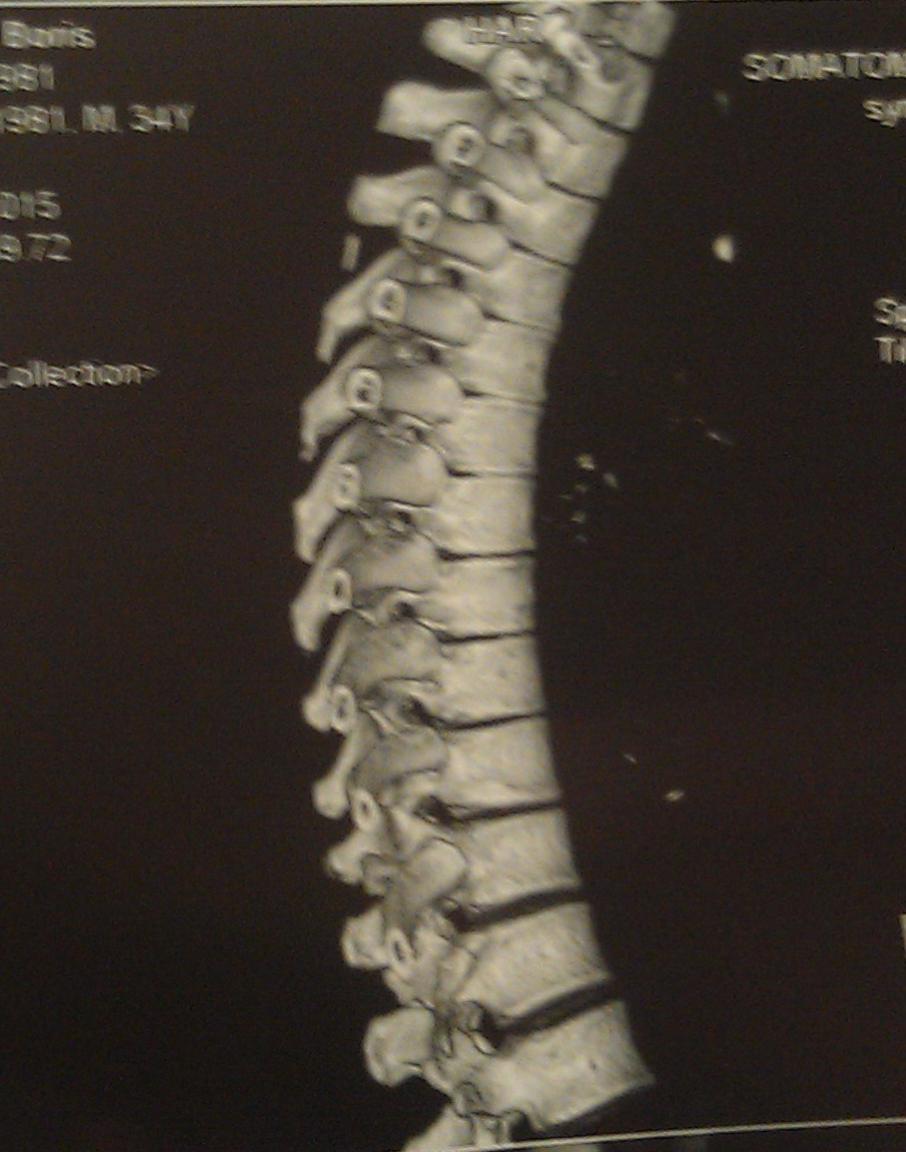

А достаточно ли плохих ревмопроб и компьютерной томограммы, где виден кифоз - чтобы поставить диагноз "болезнь Бехтерева"?

Вот моя компьютерная томограмма позвоночника.

Вложение 1182Вложение 1184Вложение 1185Вложение 1186Вложение 1183

Судя по снимкам ярко выраженный кифоз, отсюда и сдавливание легких Плохо видно, вроде срастания позвонков нет и это очень хорошо, На данном этапе желательно следить за своим прямохождением-прямосидением и упражнениями способствующими этому.Не ходить к костоломам, ну вроде как потянем-растянем-подстукнем и тд.